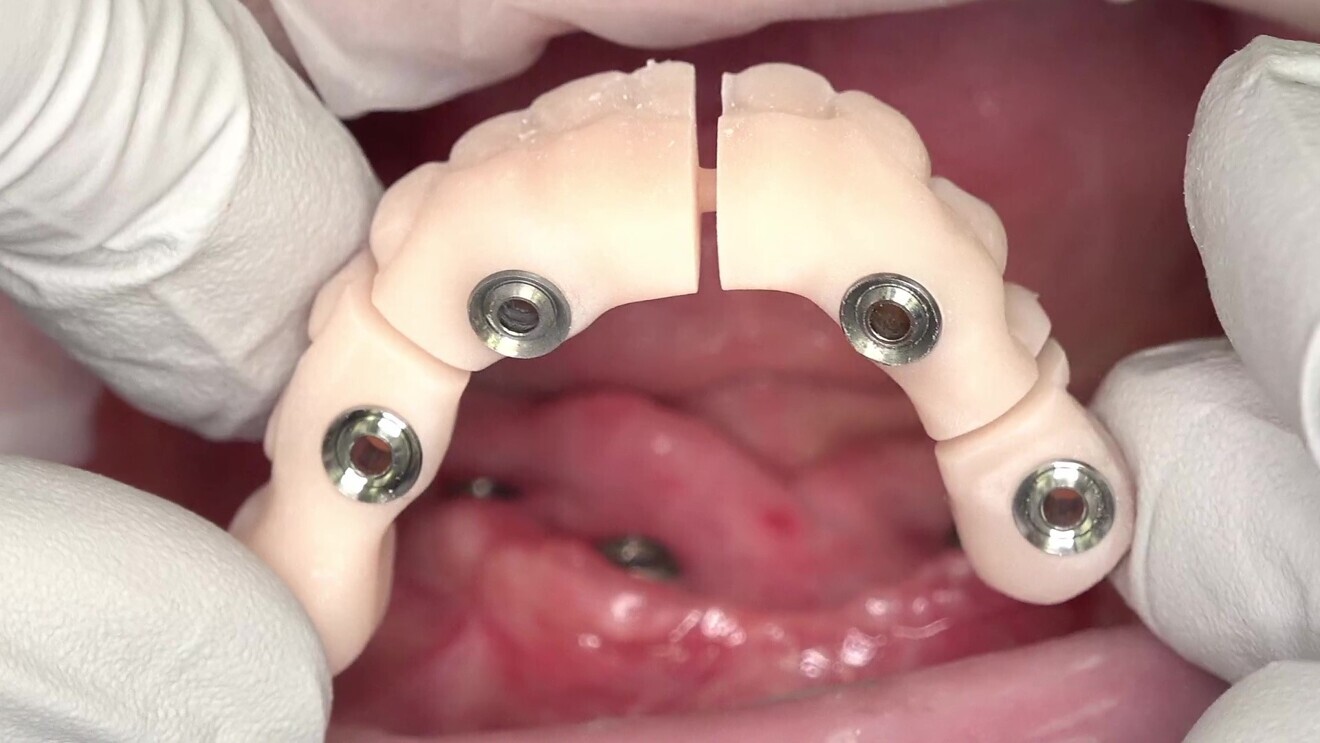

After the digitisation of the implants, two sets of 3D-printed try-ins were fabricated for both jaws. The first set, the validator set, was designed with gaps between the implant positions (Fig. 7). These gaps allowed for the detection of tension when the validator was seated, fractures occurring in the small gaps if tension was present. This step ensured that the final prostheses would fit accurately and comfortably without undue stress on the implants or surrounding tissue (Figs. 8–10). The validators had the same design as the second set of try-ins, the only difference being that the validators were cut between the implants using a virtual disc cutter and the attachment function in exocad software. It is crucial to ensure that the titanium bases or bar is firmly seated within the validator, which can preferably be achieved using resin cement. The validator should be retained with the same torque as the manufacturer recommends for the final restoration.

Fig. 7: 3D-printed validator try-in with gaps between implant positions.

Fig. 8: Seating of the validator try-in in the patient’s mouth.

Fig. 9: Validator try-in seated in the patient’s mouth.

Fig. 10: Adjusted validator try-in without fractures in the lower jaw.